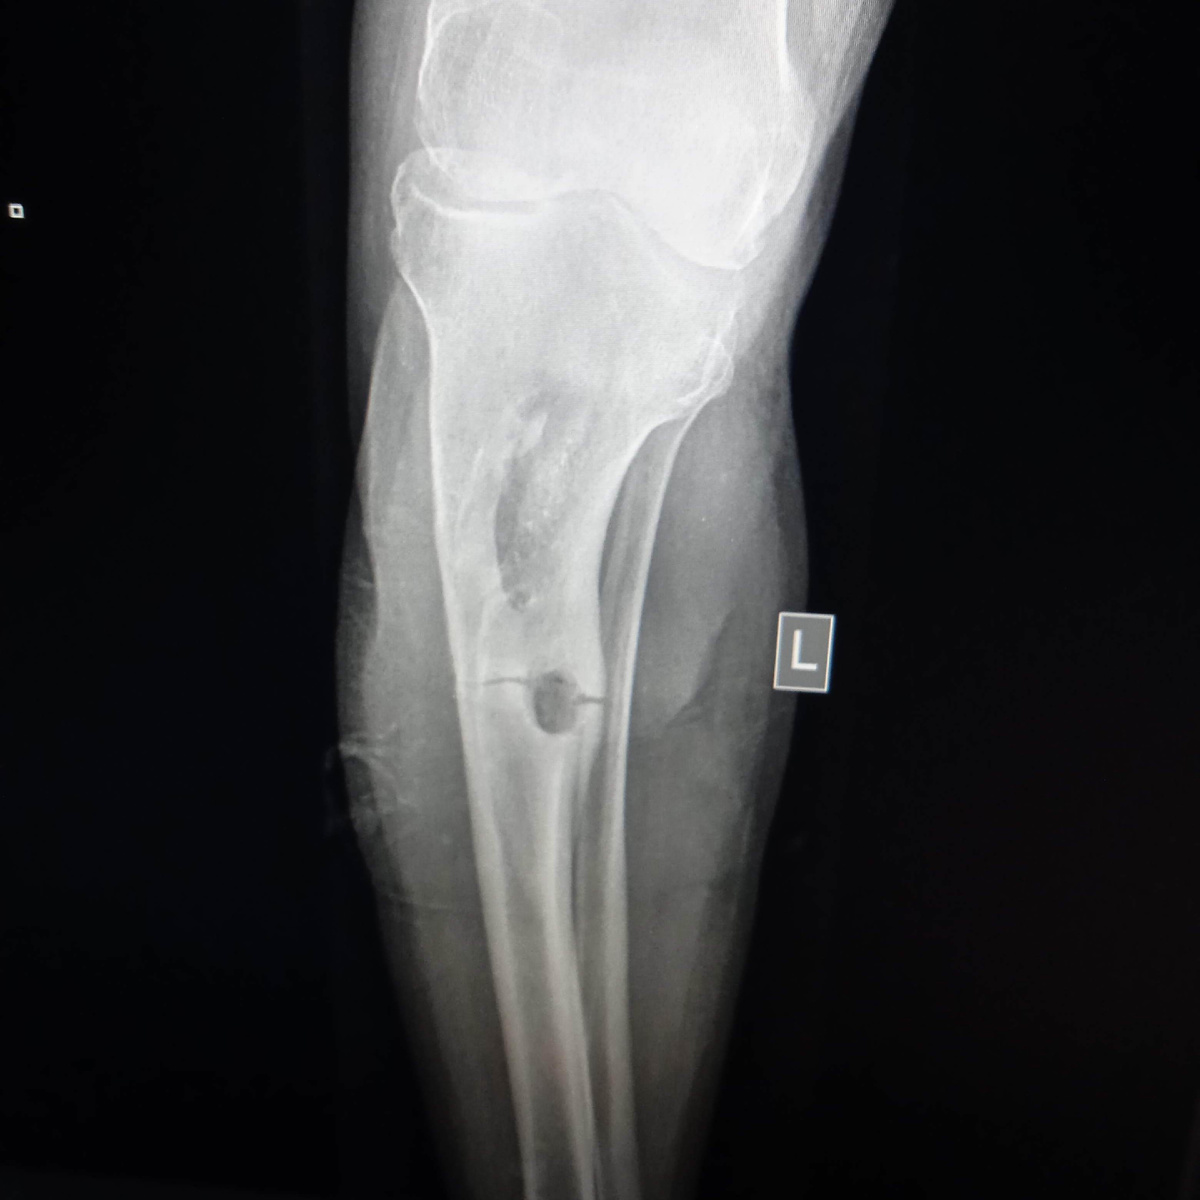

Картина остеомиелита после МОС

В 22 году женщина попала к нам в больницу после ДТП. Можно сказать, что она относительно легко отделалась, сломала обе берцовыберцовые кости на левой ноге и пяточную кость на правой стопе, и пару пястных костей сломала на руке.

Изначально ей поставили экстрамедуллярную конструкцию(аппарат Илизарова) на левые берцовой кости, в пяточную кость поставили пару гвоздей, а руку просто загипсовали, смещения костей почти не было.

Про уход за кожей в местах внедрения спиц аппарата тоже давали подробные инструкции, но пациентка через три месяца поступила с ярко выраженной картиной остеомиелита, температура, озноб, выраженная гиперемия и отёк конечностей, с очень плохими анализами крови. Рентгенография подтвердила предварительный диагноз